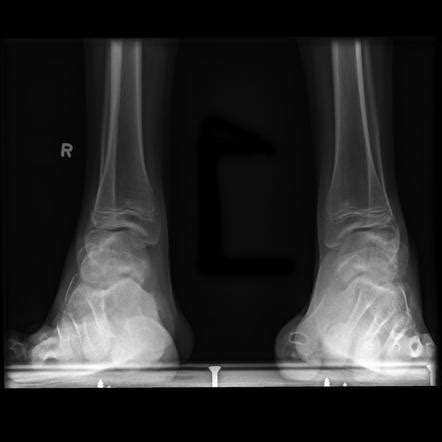

Figure 2 from New insights into the pathophysiology of pes ...

Figure 2 from New insights into the pathophysiology of pes ... from d3i71xaburhd42.cloudfront.net